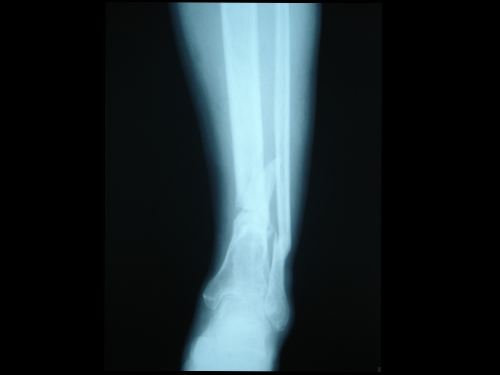

脛腓骨骨干骨折在全身骨折中最為常見。10歲以下兒童尤為多見。其中以脛骨干單骨折最多,脛腓骨干雙折次之,腓骨干單骨折最少。脛骨是連接股骨下方的支承體重的主要骨骼,腓骨是附連小腿肌肉的重要骨骼,并承擔1/6的承重。脛骨中下1/3處易于骨折。脛骨上1/3骨折移位,易壓迫腘動脈,造成小腿下段嚴重缺血壞死。脛骨中1/3骨折淤血潴留在小腿的骨筋膜室,增加室內壓力造成缺血性肌攣縮。脛骨中下1/3骨折使滋養動脈斷裂,易引起骨折 延遲愈合。